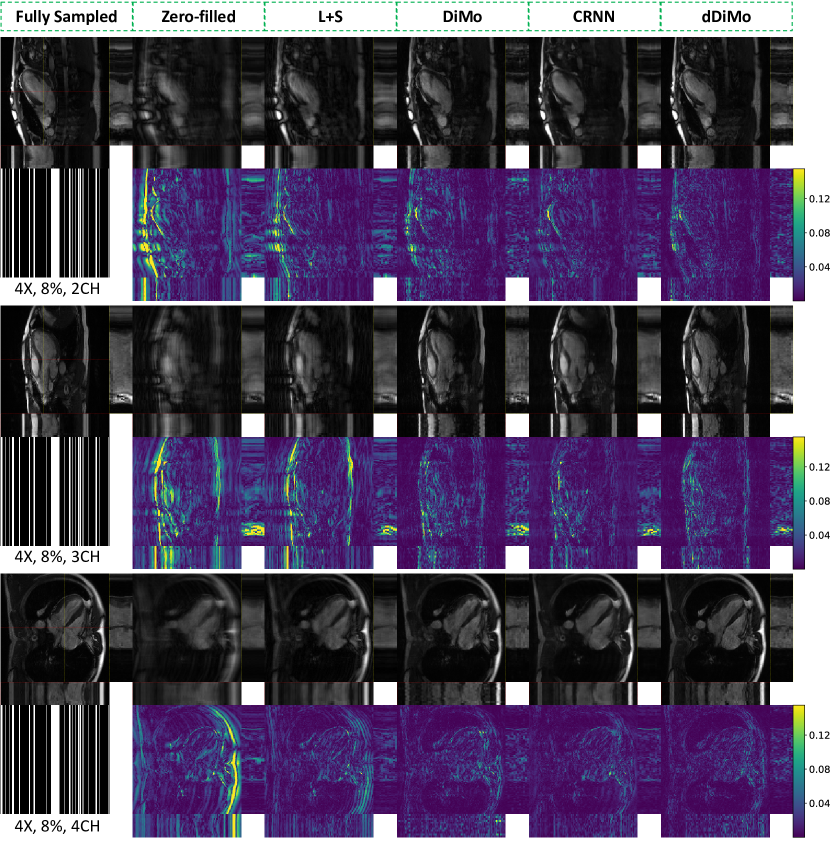

Figure S1. Qualitative comparison of different reconstruction methods in spatial and spatiotemporal dimensions, accompanied by corresponding error maps, for cardiac cine in long-axis views: two-chamber (2CH), three-chamber (3CH), and four-chamber (4CH). Spatiotemporal profiles along the yellow and red dotted lines are highlighted within yellow and red rectangles. Results are shown for an undersampling rate of 8. The proposed method demonstrates superior performance in recovering fine spatial details and preserving temporal dynamics.

Figure S2. Qualitative comparison of different reconstruction methods in spatial and spatiotemporal dimensions, accompanied by corresponding error maps, for cardiac cine in long-axis views: two-chamber (2CH), three-chamber (3CH), and four-chamber (4CH). Spatiotemporal profiles along the yellow and red dotted lines are highlighted within yellow and red rectangles. Results are presented for an undersampling rate of 10. The proposed method demonstrates superior performance in recovering fine spatial details and maintaining temporal dynamics.